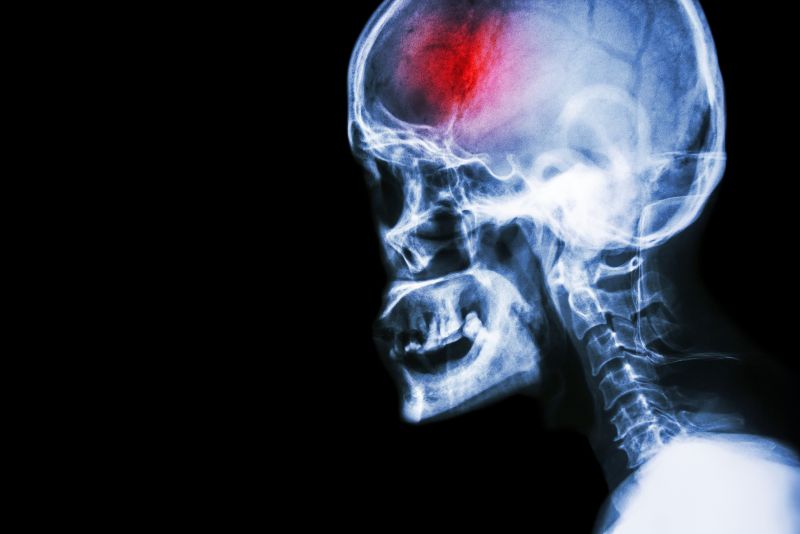

Head X-ray

A stroke (previously known as a cerebrovascular accident) when there is a decreased flow of blood to the brain from either a blockage in the blood vessels that supply the brain (ischemic stroke), or a bleed from the blood vessels that supply the brain (hemorrhagic stroke). When the blood flow to the brain is blocked it prevents the brain from getting the needed oxygen and nutrients to function. Without oxygen the brain cells can be permanently damaged or die and the physical and mental functions related to that area of the brain will be affected. A stroke is a medical emergency and rapid treatment is crucial to decreasing the damage caused by a stroke.